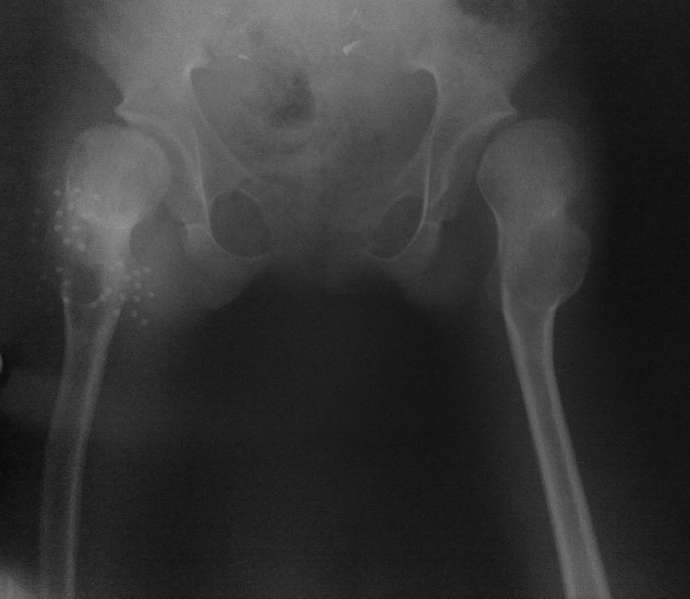

Под общим наркозом вправлен. 2 недели ребенок находился на лейкопластырном вытяжении. В связи с тяжким состоянием ребенка (диспептические явления, задержка стула, носовые кровотечения, начальные явления застойной пневмонии) вытяжение снято. сразу после чего сделано рентген контроль (фото 1). а через неделю, то есть сегодня сделан второй снимок (фото 2). Где видно повторный вывих.

На рентгенограмме видно, что в 3 месячном возрасте не была диагностирована тяжелая форма дисплазии с подвывихами, где, кроме вывиха, имеет место непролеченные диспластические суставы с обеих сторон, больше справа.

Ни скелетное, ни лейкопластырное вытяжение за бедро долго не выдержит. Даже если вправить вывих, он повторится в силу диспластичности сустава.